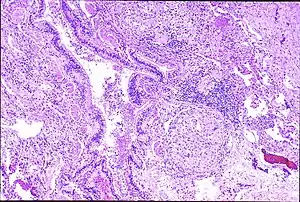

| Peribronchal non-necrotizing granuloma from berylliosis | |

Granulomas are seen in other chronic diseases, such as tuberculosis and sarcoidosis, and it can occasionally be hard to distinguish berylliosis from these disorders. However, granulomas of CBD will typically be non-caseating, i.e. not characterized by necrosis and therefore not exhibiting a cheese-like appearance grossly.[5]